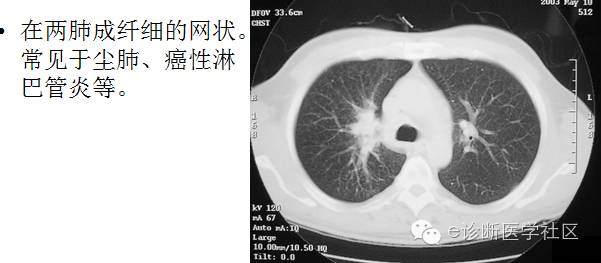

3淋巴性肺纹理增强

主要见于肺内淋巴道转移。肺转移癌的癌细胞沿支气管和静脉周围的淋巴管广泛浸润,这种改变可局限于肺门附近,也可以扩展到肺野外带,肺纹理增多增强,呈纤细的网状影,孤立的肺纹理增强,其临床价值较小,只有认真分析肺纹理增强的性质,并与其它X线征象和临床资料结合起来,才有较大的诊断价值。